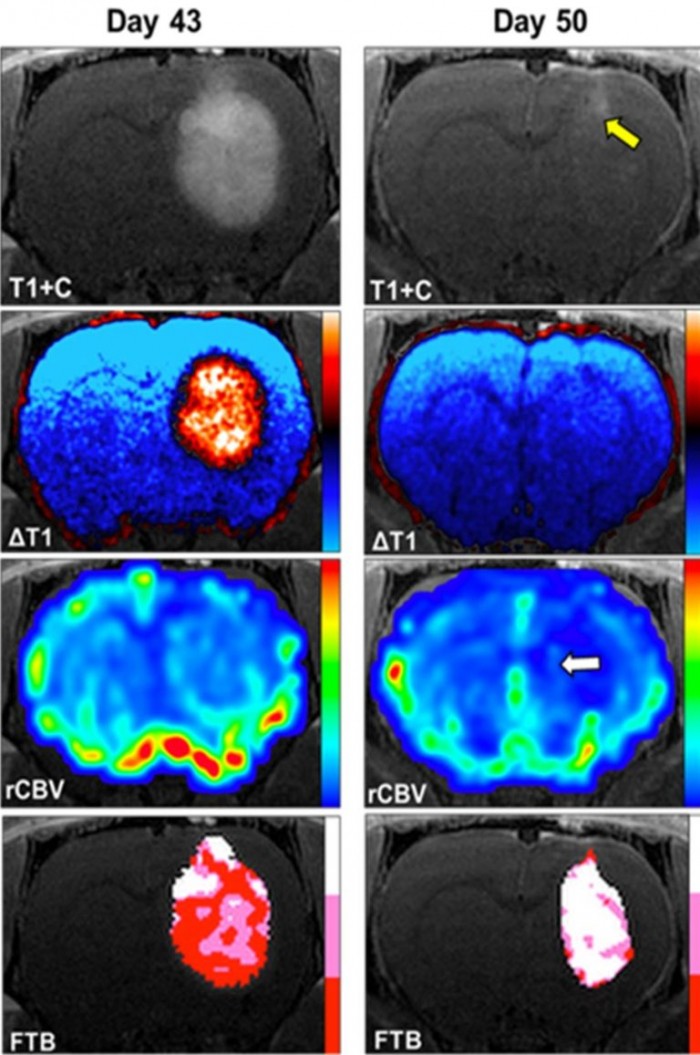

摘要: 威斯康星医学院(MCW)癌症中心研究的一种新型疗法已导致一项治疗胶质母细胞瘤的临床试验。胶质母细胞瘤是一种罕见的侵袭性脑癌,但却是成人中最常见的原发性脑肿瘤。访问: 阿里云“无影云电脑” 支持企业快速实现居家办公尽管在全球范围内进行了几十年的研究,但在延长或提高胶质母细胞瘤患者的生活质量方面只取得了渐进式的进展。治疗方案是有限的,通常包括手术、放疗和化疗的组合。现在,威斯康星州医学院的一项新的临床研究将评估一种口服的替代疗法。这种治疗方法是由Christopher Chitambar博士及其实验室领导的多年研究演变而来,研究癌症生物学中的铁依赖过程以及镓化合物针对铁代谢和阻止恶性细胞生长的机制。在临床前研究中,Chitambar博士和Kathleen Schmainda博士发现,当静脉注射麦芽酚镓(GaM)时,可显着减缓大鼠脑肿瘤模型中胶质母细胞瘤的生长。其他研究表明,口服GaM给患有胶质母细胞瘤的大鼠,可明显减少其肿瘤的大小并延长生存期。 GaM最初由哈佛大学和斯坦福大学的科学家Lawrence R. Bernstein博士开发,是一种口服形式的金属镓,在体内与铁的高度氧化形式Fe(III)有许多化学特性。众多研究铁与癌症之间关系的研究表明,由于癌细胞依赖铁来繁殖和扩散,体内铁含量的增加可能与癌症风险和严重程度的增加有关。由于镓与Fe(III)(癌细胞吸收的铁的形式)的相似性,癌细胞吸收镓而不是铁,阻止它们的繁殖,最终导致它们死亡。 “在临床前研究中发现GaM对胶质母细胞瘤具有抗癌活性是非常令人兴奋的;它为开发它作为治疗病人胶质母细胞瘤的药物打开了大门,”MCW血液学和肿瘤学部医学和生物物理学荣誉教授Christopher Chitambar博士说。他补充说:“GaM的抗癌机制也适用于其他实体肿瘤。” 麻省理工学院神经学副教授Jennifer Connelly, MD是该临床试验的首席研究员(PI),Chitambar博士担任联合PI和主席。两人都是Kathleen Schmainda博士的长期合作者,Kathleen Schmainda博士是Imaging Biometrics, LLC的联合创始人,也是脑瘤成像领域公认的领导者。 Bernstein博士作为共同研究者参与其中。这项试验由Imaging Biometrics公司赞助,Musella脑瘤基金会和MCW癌症中心也提供了支持。位于威斯康星州榆树林的Imaging Biometrics公司是IQ-AI公司的全资子公司。 Imaging Biometrics在定量脑瘤成像分析方面有十多年的经验,包括为几项国家多中心试验进行分析,它将为评估GaM的反应提供图像分析解决方案。 Imaging Biometrics公司首席执行官Michael Schmainda说:“我们正在与一个优秀的科学家和临床医生团队合作,每个人都渴望推进这项研究。” 这项试验在Froedtert和威斯康星州医学院进行,目前正在接受参与者,预计完成日期为2025年12月。